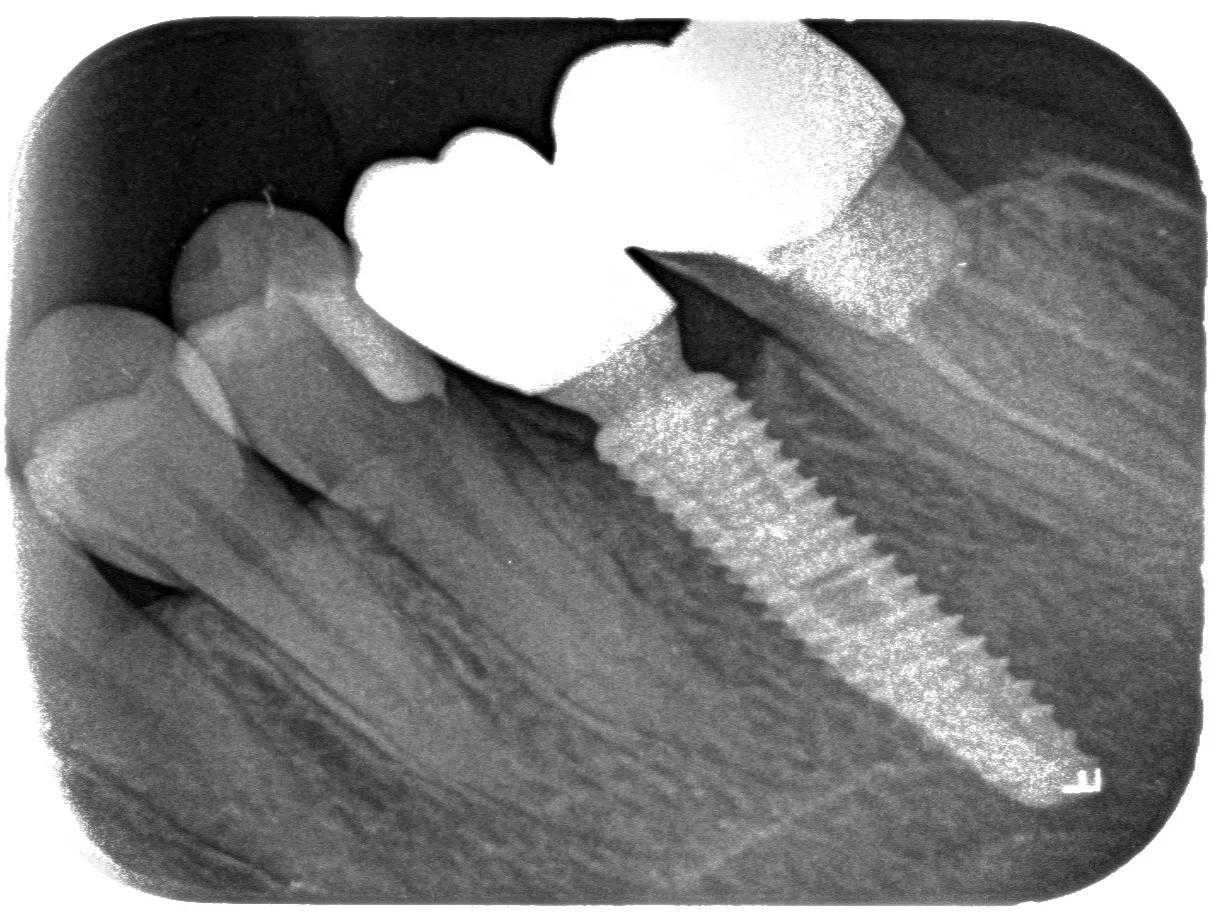

step2.

正式开始种植牙手术。在牙槽骨上制备一个孔,植入人工种植体。将牙骨床内严密缝合,大约一个星期后可以拆线。这次大概2个半月--3个月)